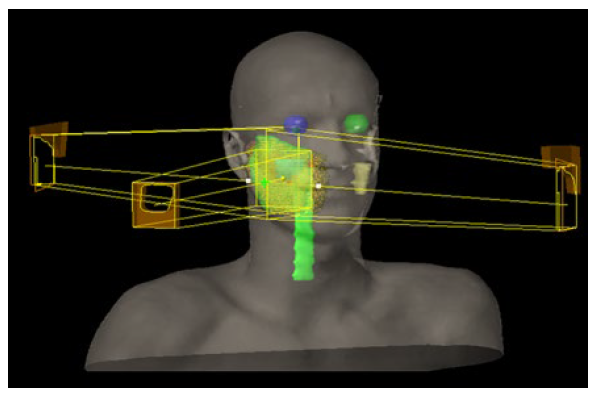

Between August and September 2015, the patient received adjuvant three-dimensional conformal radiotherapy (3D-CRT), with 50 Gy in 25 fractions, directed to the right hemiface, followed by a boost of 10 Gy in 5 fractions to the tumor bed (Fig. 1), without significant complications.